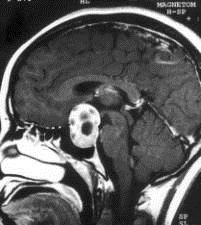

问题 病历摘要:??患者男性,35岁。性功能减退2年,视力下降6月。既往体健。体检:神清,皮肤细腻,毛发稀疏。视力左眼0.3,右眼0.5,双瞳等大等圆,直径3.5mm,对光反射稍迟钝,双颞侧偏盲,双眼底视神经乳头原发性萎缩,余神经系统未见异常。 关于鞍区周围的神经血管间隙的叙述哪些是正确的?

选项 A.视交叉前间隙为间隙1 B.视交叉后间隙为间隙2 C.视神经-颈内动脉间隙为间隙2 D.视神经-颈内动脉间隙为间隙3 E.颈内动脉外侧间隙为间隙3 F.颈内动脉外侧间隙为间隙4 G.终板池间隙为间隙4 H.终板池间隙为间隙5